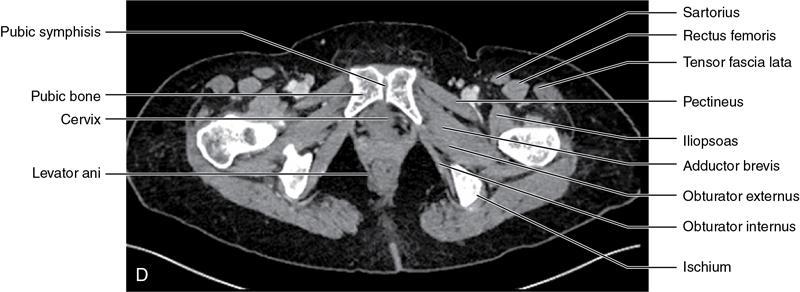

CROSS SECTIONAL ANATOMY OF ABDOMEN Satya Jha NORMAL ANATOMY OF ABDOMEN AND PELVIS Amandeep Singh The two major surfaces: The anterior and posterior layers of the coronary ligament converge on bare area (not covered by peritoneum). Its right and left margins form the right and left triangular ligaments. The right triangular ligament extends toward the diaphragm and separates right subphrenic space from right subhepatic space. The left triangular ligament gives tracts extending to the diaphragm and falciform ligament and does not compartmentalize the left subphrenic space. Ligamentum teres or the obliterated umblical vein is contained in falciform ligament which attaches the liver to anterior abdominal wall. The main portal vein, the proper hepatic artery and the common bile duct are contained within investing peritoneal folds of hepatoduodenal ligament at the porta hepatis (Fig. 7.2.2.1). Liver is divided into eight segments which are functionally independent and have their own vascular supply and biliary drainage. Arterial circulation: The branches of the hepatic artery accompanying the portal veins. Hepatic venous system: The right, middle, and left hepatic veins draining into IVC (Figs. 7.2.2.2 and 7.2.2.3). The gallbladder is a blind pear-shaped muscular membranous sac which is an embryologic derivative of the foregut, is a pouch lying along the undersurface of the liver. The gallbladder fossa is located in the plane of the interlobar fissure, which lies between the right and left hepatic lobes. Its major function is to store and concentrate bile which is produced by the liver. It measures approximately 4 cm in diameter when it is normally distended. Gallbladder is a smaller tubular structure in contracted state. The normal gallbladder wall thickness ranges from 1 to 3 mm. The gallbladder is divided into the fundus, body and neck. Infundibulum is present in the region of neck of the gallbladder, which is called the Hartmann pouch, where gallstones are usually impacted. Intrahepatic biliary radicles (IHBRs) scattered throughout the liver get confluent towards the hilum. They unite to form the right and left main hepatic ducts which further unite to form common hepatic duct (CHD) at the hilum. Common bile duct is formed by the union of cystic duct with common hepatic duct. The main pancreatic duct is joined with the common bile duct to form the ampulla of Vater at the major duodenal papilla (Figs. 7.2.2.4 and 7.2.2.5). Pancreas is located in anterior pararenal space of retroperitoneum anterior to perirenal (Gerota’s) fascia and posterior to parietal peritoneum. It is divided into head, uncinate process, neck, body and tail from right to left. Pancreas lies anterior to portal vein, which marks the point of transition between the body and neck. The region between head of pancreas and second and third parts of duodenum is known as the pancreatic groove. In postnephrectomy cases or with agenesis of kidney or ectopic kidney, pancreas moves posteriorly to partially fill in the empty renal fossa; its soft tissue density should not be mistaken for recurrent tumour. It is located in the pancreatic groove and is bounded superiorly by the duodenal bulb, laterally by second portion of duodenum, inferiorly by third portion of duodenum, medially by superior mesenteric vein and anterior to inferior vena cava. It is a wedge or wedge shaped lying posterior to superior mesenteric artery and vein. It is an imaginary junction between the head and body and lies directly over the junction of the splenic vein and superior mesenteric vein. It is located posterior to the lesser sac and anterior to the aorta, left adrenal gland, left kidney, and renal vessels and runs obliquely upward to the left of the superior mesenteric vessels. It is situated median to the colonic flexure and anterior to the left kidney. It is located in close proximity to the splenic hilum without a notable relation with the body of pancreas. It is seen anterior to the left kidney and median to the colonic flexure. The distal part of the tail passes between the peritoneal layers of the splenorenal ligament (Fig. 7.2.2.6 and 7.2.2.7).